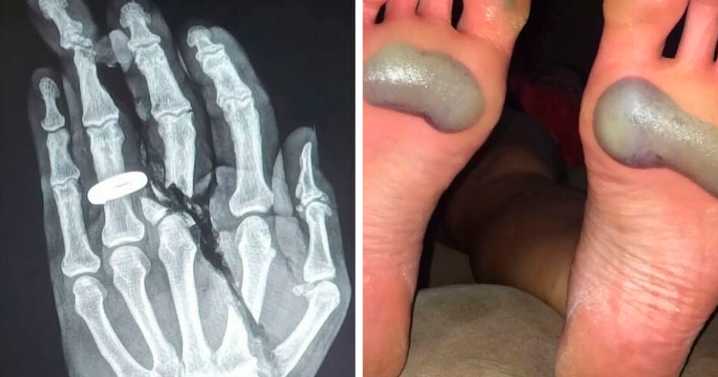

If you’ve ever wanted to be a doctor or know someone who works in healthcare, you probably know how bizarre and even scary the medical field and the human body can be. The world’s medical history is full of eerie events, powerful breakthroughs, and moments that make you wonder whether you’re stuck in an episode of Black Mirror or The Twilight Zone.

The ‘Creepy Medical’ account on Instagram features some of the most bizarre and chilling medical pics and facts. We’ve collected some of the weirdest ones to share with you, and you can check them out by scrolling down.

Warning: keep in mind that you may find some of these images and topics incredibly uncomfortable and gross.